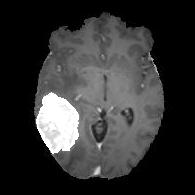

We argue that the sub-optimal paradigm of processing different abstractions within a single CNN pipeline can be remedied through the effective processing of information in a structured manner. Consequently, we devise strategies for disentangling the edge and texture information within a single training pipeline. Figure 2 illustrates how our proposed module, dubbed EG-CNN, can be paired with any existing CNN encoder-decoder to improve segmentation quality near intensity edges. We have applied our EG-CNN to the tasks of brain and liver tumor segmentation in medical images (Figure 3).

(1) Brain MR (2) Liver MR (3) Liver CT (4) Lung CT